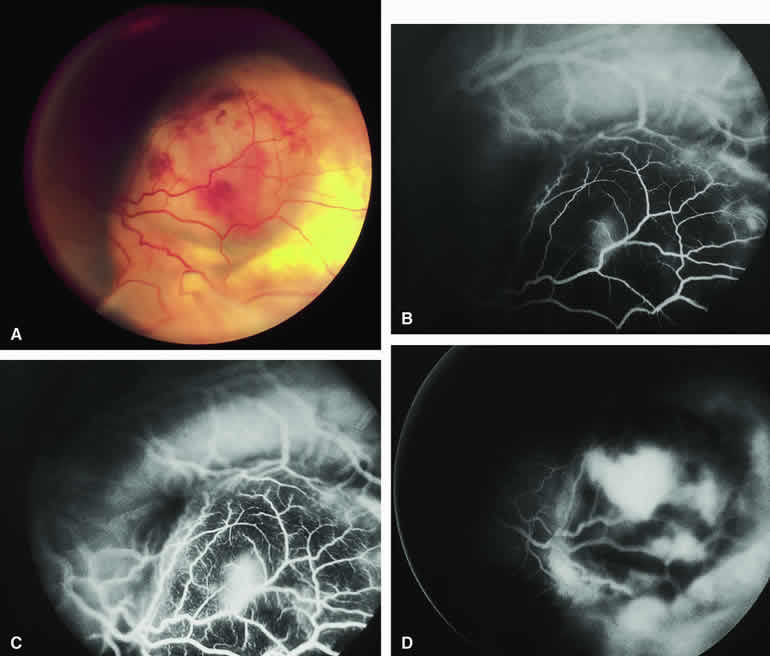

Choroidal Nevus with Drusen and Clumps of RPE Hyperplasia

If a choroidal nevus has drusen and RPE alterations on its surface (see Fig. 4A), fluorescein angiography (Fig. 4B, C, and D) tends to show patchy or stippled window defect hyperfluorescence corresponding to foci of RPE depigmentation, fluorescence blockage by clumps of RPE hyperplasia on the surface of the lesion, and late staining of at least some of the drusen. These features are not usually as evident on ICG angiography as they are on fluorescein angiography.